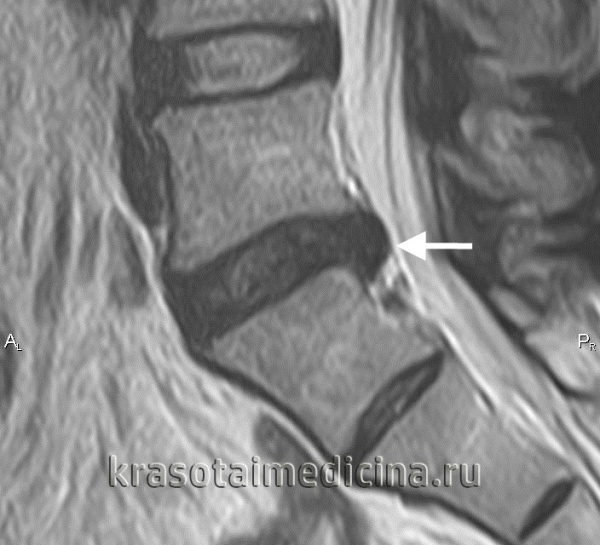

14.09.2018 было проведено МРТ ПКОП (пояснично-крестцового отдела позвоночника): ⠀• форма тел позвонков изменена за счёт деформации замыкательных пластин, краевых костных разрастаний по передне-задним и боковым поверхностям тел L3-L5 позвонков; ⠀• грыжа размером до 0,6 см распространяется в левое межпозвонковое отверстие и вниз на всю высоту тела L5 позвонка, она сжимает левый боковой корешок; ⠀• задняя парамедианная протрузия диска L5-S1 размерами до 0,3 см деформирует дуральный мешок, при этом структуры самого мешка не изменены; ⠀• определяется грибовидная деформация дугоотросчатых суставов L4-S1 с субхондральным склерозом и сужением соответствующих суставных щелей — проявление спондилоартроза; ⠀• физиологический поясничный изгиб позвоночника сохранён. Заключение: МР картина распространённых дегенеративно-дистрофических изменений сегментов пояснично-крестцового отдела позвоночника и секвестрированной парамедианной левосторонней сублигаментарной с каудальной направленностью, грыжи диска L4-L5 и спондилоартроза. После консультации нейрохирурга рекомендовано оперативное лечение — расширенная интерламинэктомия и микродискэктомия L4-L5 (удаление межпозвонкового диска и грыжи), а также секвестрэктомия (удаление омертвевшей костной ткани). Операция запланирована на 27.09.2018.